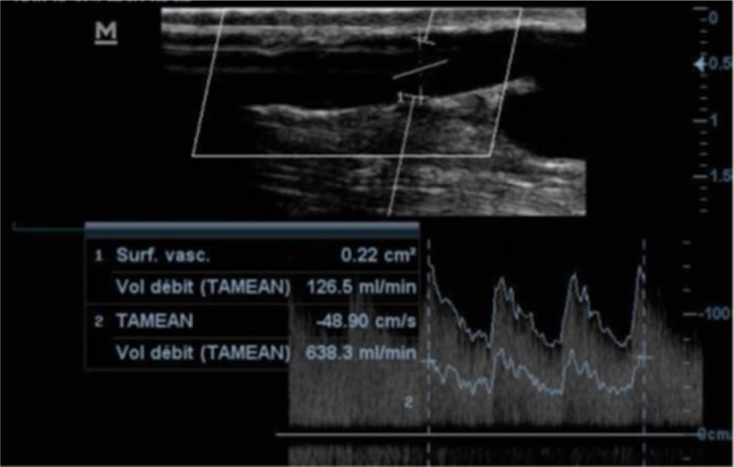

Results: Between 1 July and 31 August 2022, we recruited a total of 41 participants, of whom 56.1% were males. The mean age of the participants was 48.39 years. Radiocephalic (76%) and brachiocephalic (24%) arteriovenous fistulas were the only types present. The mean flow volume in the arteriovenous fistulas was 680.47 (365.98) ml/min, with 34.1% of the fistulas having a low flow volume. Also, 56.1% of the arteriovenous fistulas were stenosed, with the main site of stenosis being the juxta-anastomotic segment of the efferent vein. Aneurysms (53.7%), reverse flow (51.2%), venous luminal flaps (22%), and thrombus (17.1%) were the most common complications identified in the study population, with 78.05% of the arteriovenous fistulas having at least one complication. Factors associated with arteriovenous fistula stenosis included the patient body mass index and the radiocephalic fistula type. Diabetes, aneurysms, and luminal venous flaps were found to be associated with low flow volume.